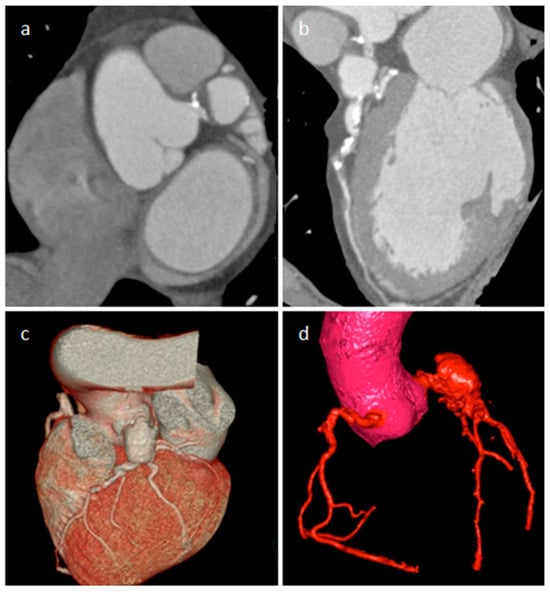

| Coronary artery aneurisms | Adulthood | AV groove | Asymptomatic | Vascular mass | AV groove mass | Dilatation, thrombus, fistula | Vascular enhancement |

3.5. Coronary Artery Aneurism (CAA)